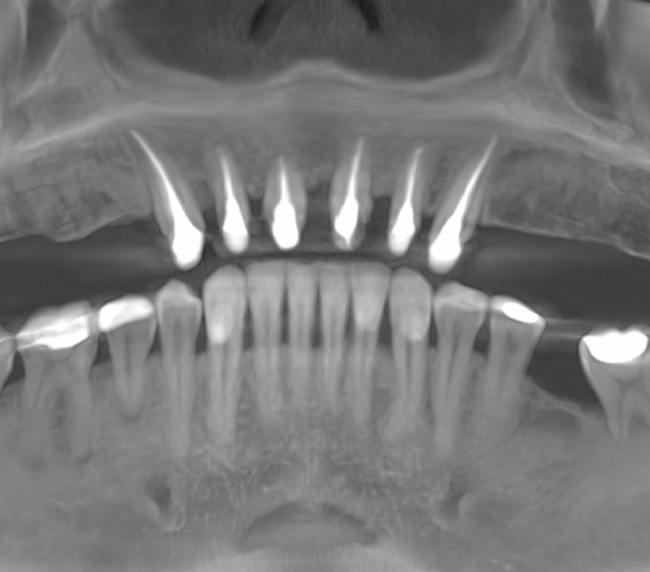

Reabilitarea complexă în stomatologie presupune refacerea completă a sistemului dentoalveolar, atât din punct de vedere funcțional, cât și estetic. Procesul începe cu o examinare detaliată a cavității bucale, interpretarea investigațiilor imagistice (CBCT), evaluarea musculaturii, articulațiilor temporomandibulare și a parametrilor estetici.

Tomografii (CBCT)

Caz 2